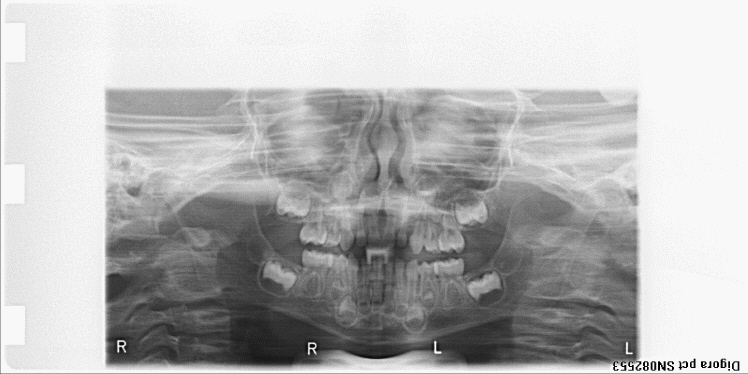

bilan des radiographies début et fin de traitement